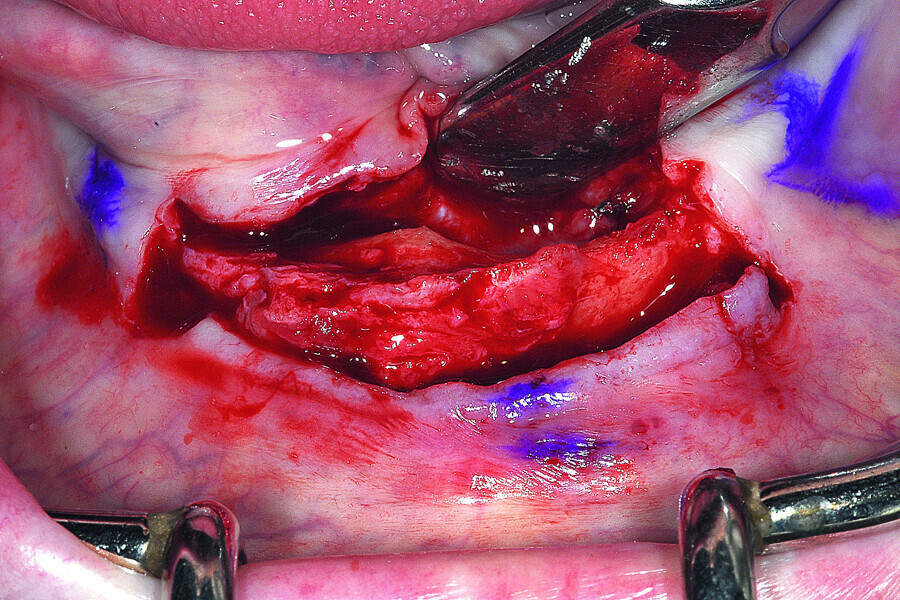

Fig. 13: A full thickness mucoperiosteal flap exposed the knifeedged ridge of the mandibular symphysis.

Fig. 14: The broken drill was located lingual to the bony crest of the mandible.

Fig. 15: The anterior symphysis revealing the anterior ‘hollow’ symphysis.